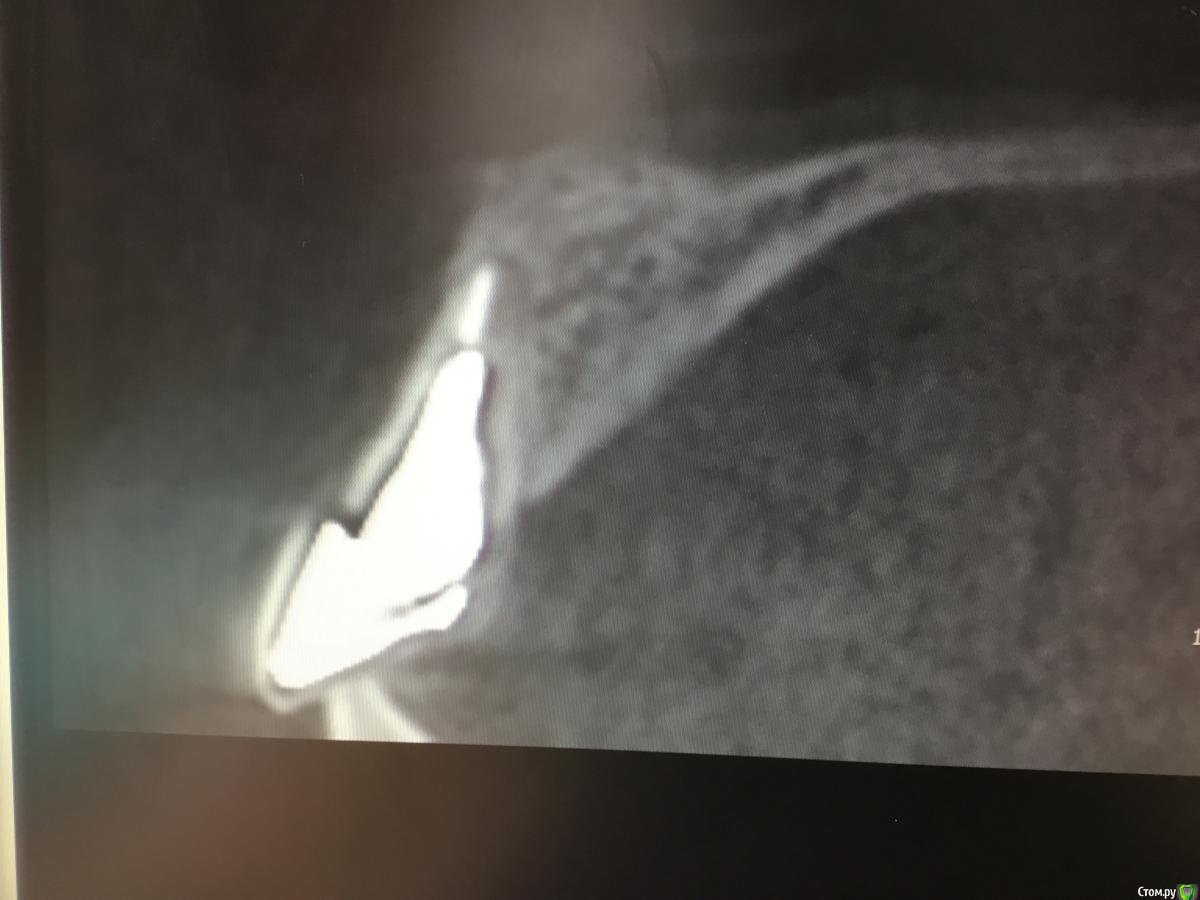

Zorrro Опубликовано 28 февраля, 2016 Поделиться Опубликовано 28 февраля, 2016 Пациента прислали на консультацию с кт. Огромная квк,ожидаемая трещина,локально гиперемия,подвижность коронки.Назначили аб терапию и записались на операцию через 2 дня.К сожалению нет фотодокументации с первой консультацией.Альтернативой немедленной нагрузки с костной и мягкотканной пластикой,были отсроченные костные блоки,с двухэтапным протоколом имплантации и тд и тп.С вероятным коллапсом мягких тканей,турбомобилизацией и прочими неприятными сопутствующими манипуляциями растянутыми по времени,а самое главное без ясного и прогнозируемого результата…короче решили рискнуть. Ссылка на комментарий

doca Опубликовано 28 февраля, 2016 Поделиться Опубликовано 28 февраля, 2016 Пациента прислали на консультацию с кт. image.jpegimage.jpegОгромная квк,ожидаемая трещина,локально гиперемия,подвижность коронки.Назначили аб терапию и записались на операцию через 2 дня.К сожалению нет фотодокументации с первой консультацией.Альтернативой немедленной нагрузки с костной и мягкотканной пластикой,были отсроченные костные блоки,с двухэтапным протоколом имплантации и тд и тп.С вероятным коллапсом мягких тканей,турбомобилизацией и прочими неприятными сопутствующими манипуляциями растянутыми по времени,а самое главное без ясного и прогнозируемого результата…короче решили рискнуть.И? 2 Ссылка на комментарий

Доктор Дмитрий Опубликовано 28 февраля, 2016 Поделиться Опубликовано 28 февраля, 2016 А в реальности что с вестибулярного кортикакой? Её вообще нет? Ссылка на комментарий

Zorrro Опубликовано 28 февраля, 2016 Автор Поделиться Опубликовано 28 февраля, 2016 А в реальности что с вестибулярного кортикакой? Её вообще нет?Вообще,то есть совсем. Ссылка на комментарий

Игорь Пеликан Опубликовано 29 февраля, 2016 Поделиться Опубликовано 29 февраля, 2016 (изменено) Вообще,то есть совсем. Если вестибулярной пластинки не бьіло,на кт похоже нет,и вьі засьіпали ету полость остепластом без ауто ,то ее и сейчас там нету,только мясо,из за етого и рецессия Изменено 29 февраля, 2016 пользователем Игорь Пеликан Ссылка на комментарий

Доктор Дмитрий Опубликовано 1 марта, 2016 Поделиться Опубликовано 1 марта, 2016 Кт после ещё нету,а качество его вполне хорошее (pointnix ).просто срезы кт в первом посте это фото экрана сделанное планшетом.в чём враньё не понял?У вас на кт нет вестибулярного кортикалки лунки Ссылка на комментарий

Zorrro Опубликовано 1 марта, 2016 Автор Поделиться Опубликовано 1 марта, 2016 А хотелось бы чтобы клиническая картина соответствовала рентгенологическое, вы ведь говорите что кортикалка была.Перечитайте,пожалуйста,где я написал,что кортикалка есть?Наоборот писал,что в проекции 21 её нету,на кт её тоже нету.во время операции тоже не заметил.может вы неправильно меня поняли или я что-то не так написал? Ссылка на комментарий